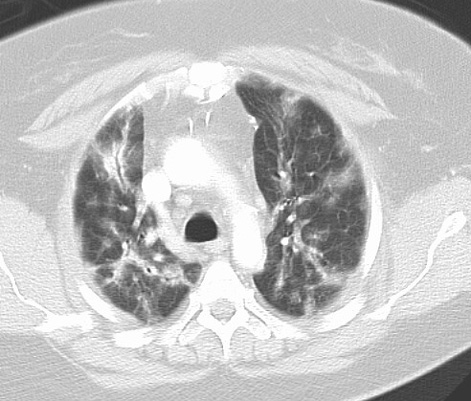

Bronchiolitis obliterans with organizing pneumonia (BOOP) is a histologic description and not a specific diagnosis. BOOP represents a proliferative bronchiolitis associated with organizing pneumonia in the surrounding lung parenchyma.

BOOP presenting with pulmonary nodules

BOOP case 2

Cryptogenic Organizing Pneumonia